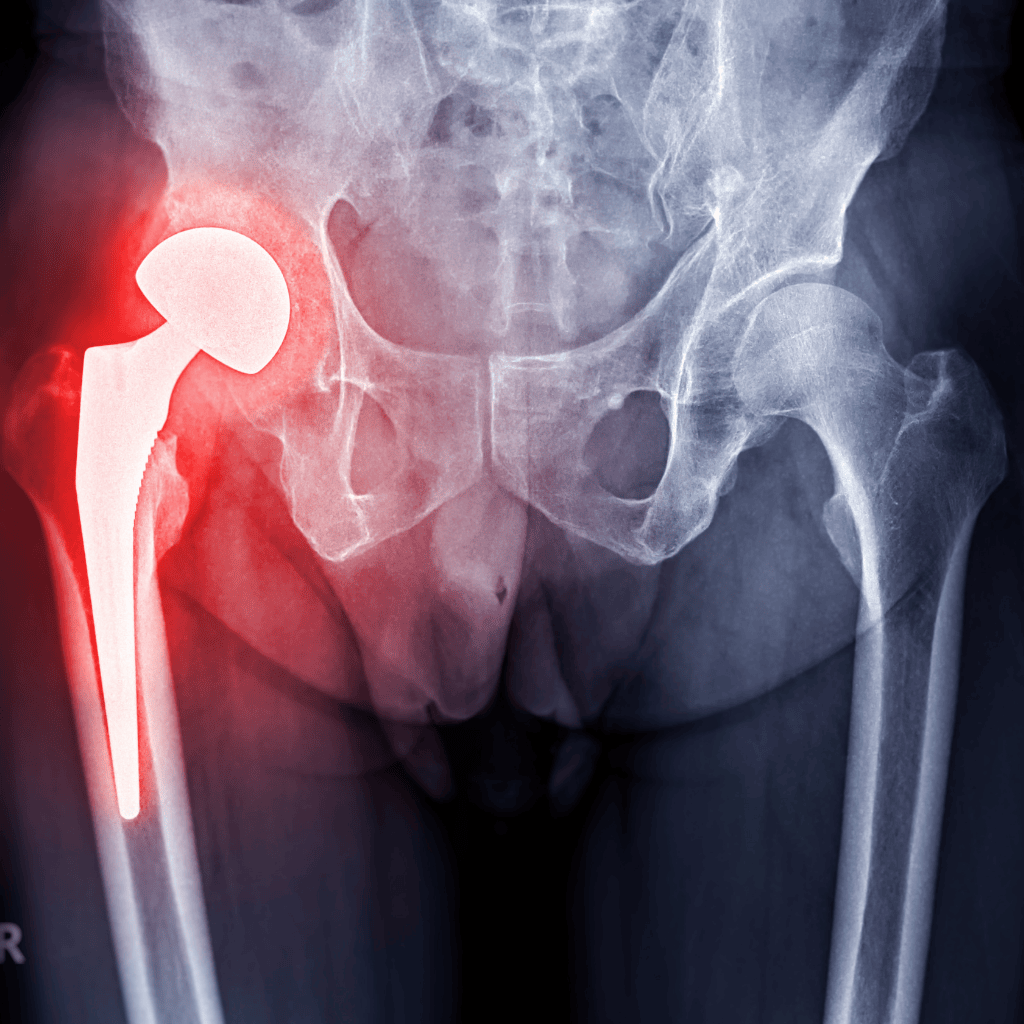

Veterans may benefit from injections into the knee, hip, ankle, or shoulder, all areas where degenerative pain can severely affect quality of life. Unlike other options, LIPO-STEM DUO™ uses no synthetic chemicals, no expanded cells, and no foreign substances, just your body, helping itself.